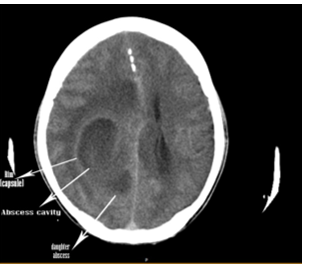

CT (computed tomography) brain revealed a large abscess cavity in the parietal region as in Figures 5, 6 and 7. The abscess was aspirated via burr-hole and cultures were found to be negative. He was given ceftriaxone 1g IV twice daily, amickacin 500 mg IV twice daily with tablet phenytoin sodium 100 mg twice daily for 2 weeks. He was symptom free and advised periodic follow up. On 1 year follow up, the patient was asymptomatic without any sequelae and advised corrective surgery for the cardiac anomaly at the earliest.

Brain abscess is an encapsulated inflammation and can be easily diagnosed by CT scan. The CT appearance of an abscess is that of a well-defined hypodense area showing ring enhancement and accompanied by extensive perifocal edema and mass effect. The ring enhancement on the CT scan surrounding a central necrotic cavity as in Figure 5 is an abscess. The appearance of enhancing rim, the capsule of the abscess enhances and it is variable. The rim is formed probably by collagen and inflammation due to free radicals and micro hemorrhages in the abscess. The abscess tends to grow towards white matter, away from the better vascularized grey matter, with thinning of the medial wall. The preferential deposits of collagen on the outer edge of the abscess is thought to be due to the vascularization of grey matter. The zone of inflammation is significantly thicker in tuberculous as compared to pyogenic abscess. The neuroimaging features of brain abscess vary with lesion stage as shown in Table 3. During the cerebritis stage (local suppurative encephalitis or immature abscess), ring enhancement may be absent or incomplete. Abscesses with a more nodular rim are often mistaken for neoplasm. Brain abscesses tend to have a smooth, thin-walled capsule and it is more irregular in tumors. In contrast to tumor, the abscess rim is typically thicker near the cortex and thinnest near the ependyma. Early capsule stage is characterized by formation of a distinct collagenous capsule, which is well delineated, relatively thin, uniform and continuous. The uniformely enhancing capsule is typical of a mature abscess. The abscess gradually shrink, peripheral edema diminishes and then disappears in the late capsule stage.

The apparent budding of smaller, ‘daughter’ lesion from the main mass is called as “daughter abscess”. In about 50% of cases, the medial wall of an abscess is thinner than the lateral one and is thought to be due to the relatively poor vascular supply of the white matter. This explains the tendency of abscess to rupture into the ventricles and the development of secondary abscesses (daughter abscess) medially [45] may be seen near the primary lesion as in Figures 6 and 7. In deep seated, multiloculated and periventricular abscesses, a reduction of 1 mm in the distance between the ventricle and brain abscess wall increases the rupture rate by 10% [46]. Smooth, < 5>